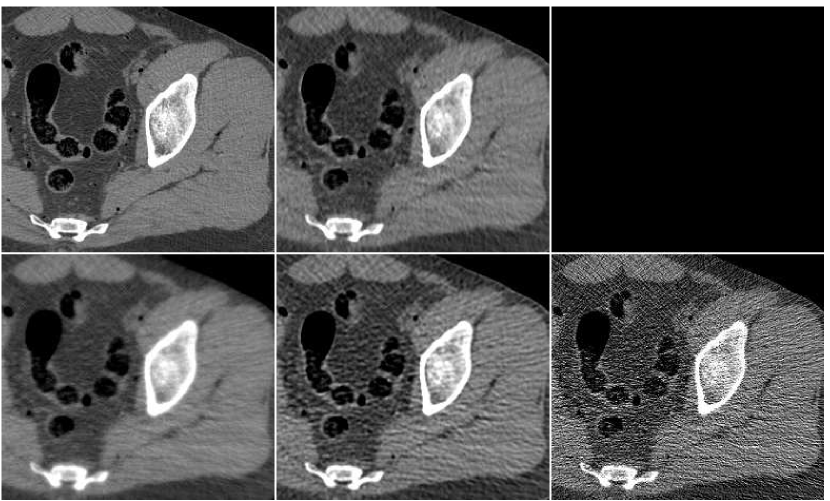

In order to test the robustness of the training results, we apply the ANN trained with the thigh sections, for a reconstruction of images of other body parts – sections of the head and the abdomen. Reconstruction results are presented in Figure 13 in the same order as in the previous comparison: middle image in the upper row is the result of fusion, which components are presented in the lower row. The head reconstruction is improved substantially by the fusion process, as visual observation shows. However, the SNR values (given in Table II) point to the favor of the PWLS image corresponding to iterations (lower middle image). The highest SSIM value does belong to the fusion result, though. In the case of the abdomen section, the fusion image is similar to the -iterations version but contains less noise; its quantitative measures are somewhat better than those of the individual PWLS images.